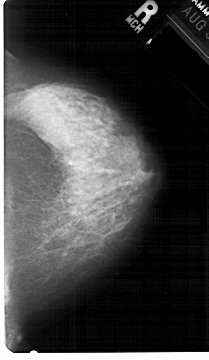

A_1396_1.RIGHT_CC

RIGHT_CC LINES 5386 PIXELS_PER_LINE 3121 BITS_PER_PIXEL 12 RESOLUTION 43.5 NON_OVERLAY